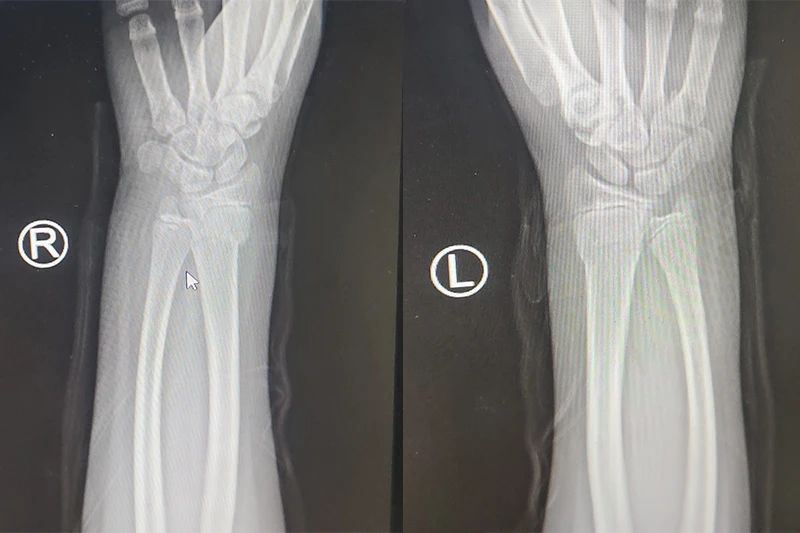

2、股骨頸骨折、轉子間骨折、骨盆及四肢骨折、脫位等。